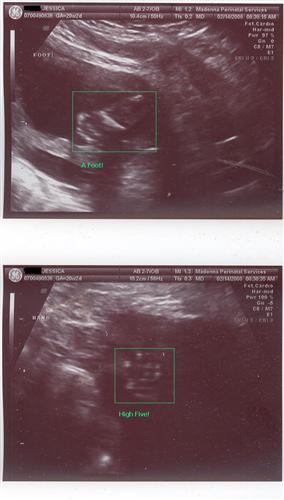

08BabySurprise

My Life. My Everything.

Member since 10/07 9151 total posts

Name:

|

Re: Sono pics... can i see your 20 week ones?

Here are a few from my 20 week sono. Fingers crossed the pictures will post... Image Attachment(s):

Message edited 2/21/2008 10:45:39 AM.